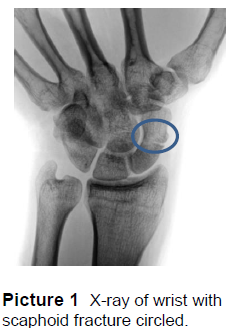

X-rays of the wrist are taken to see if a fracture is present (Picture 1). This scaphoid fracture would be called a waist fracture based on its location in the middle third of the bone.

If the fracture is located in the bottom third of the bone it is known as a ‘proximal pole’ fracture.

On the top third of the bone, it is a ‘distal pole’ fracture. Where it is located will play a role in the treatment plan of the fracture.